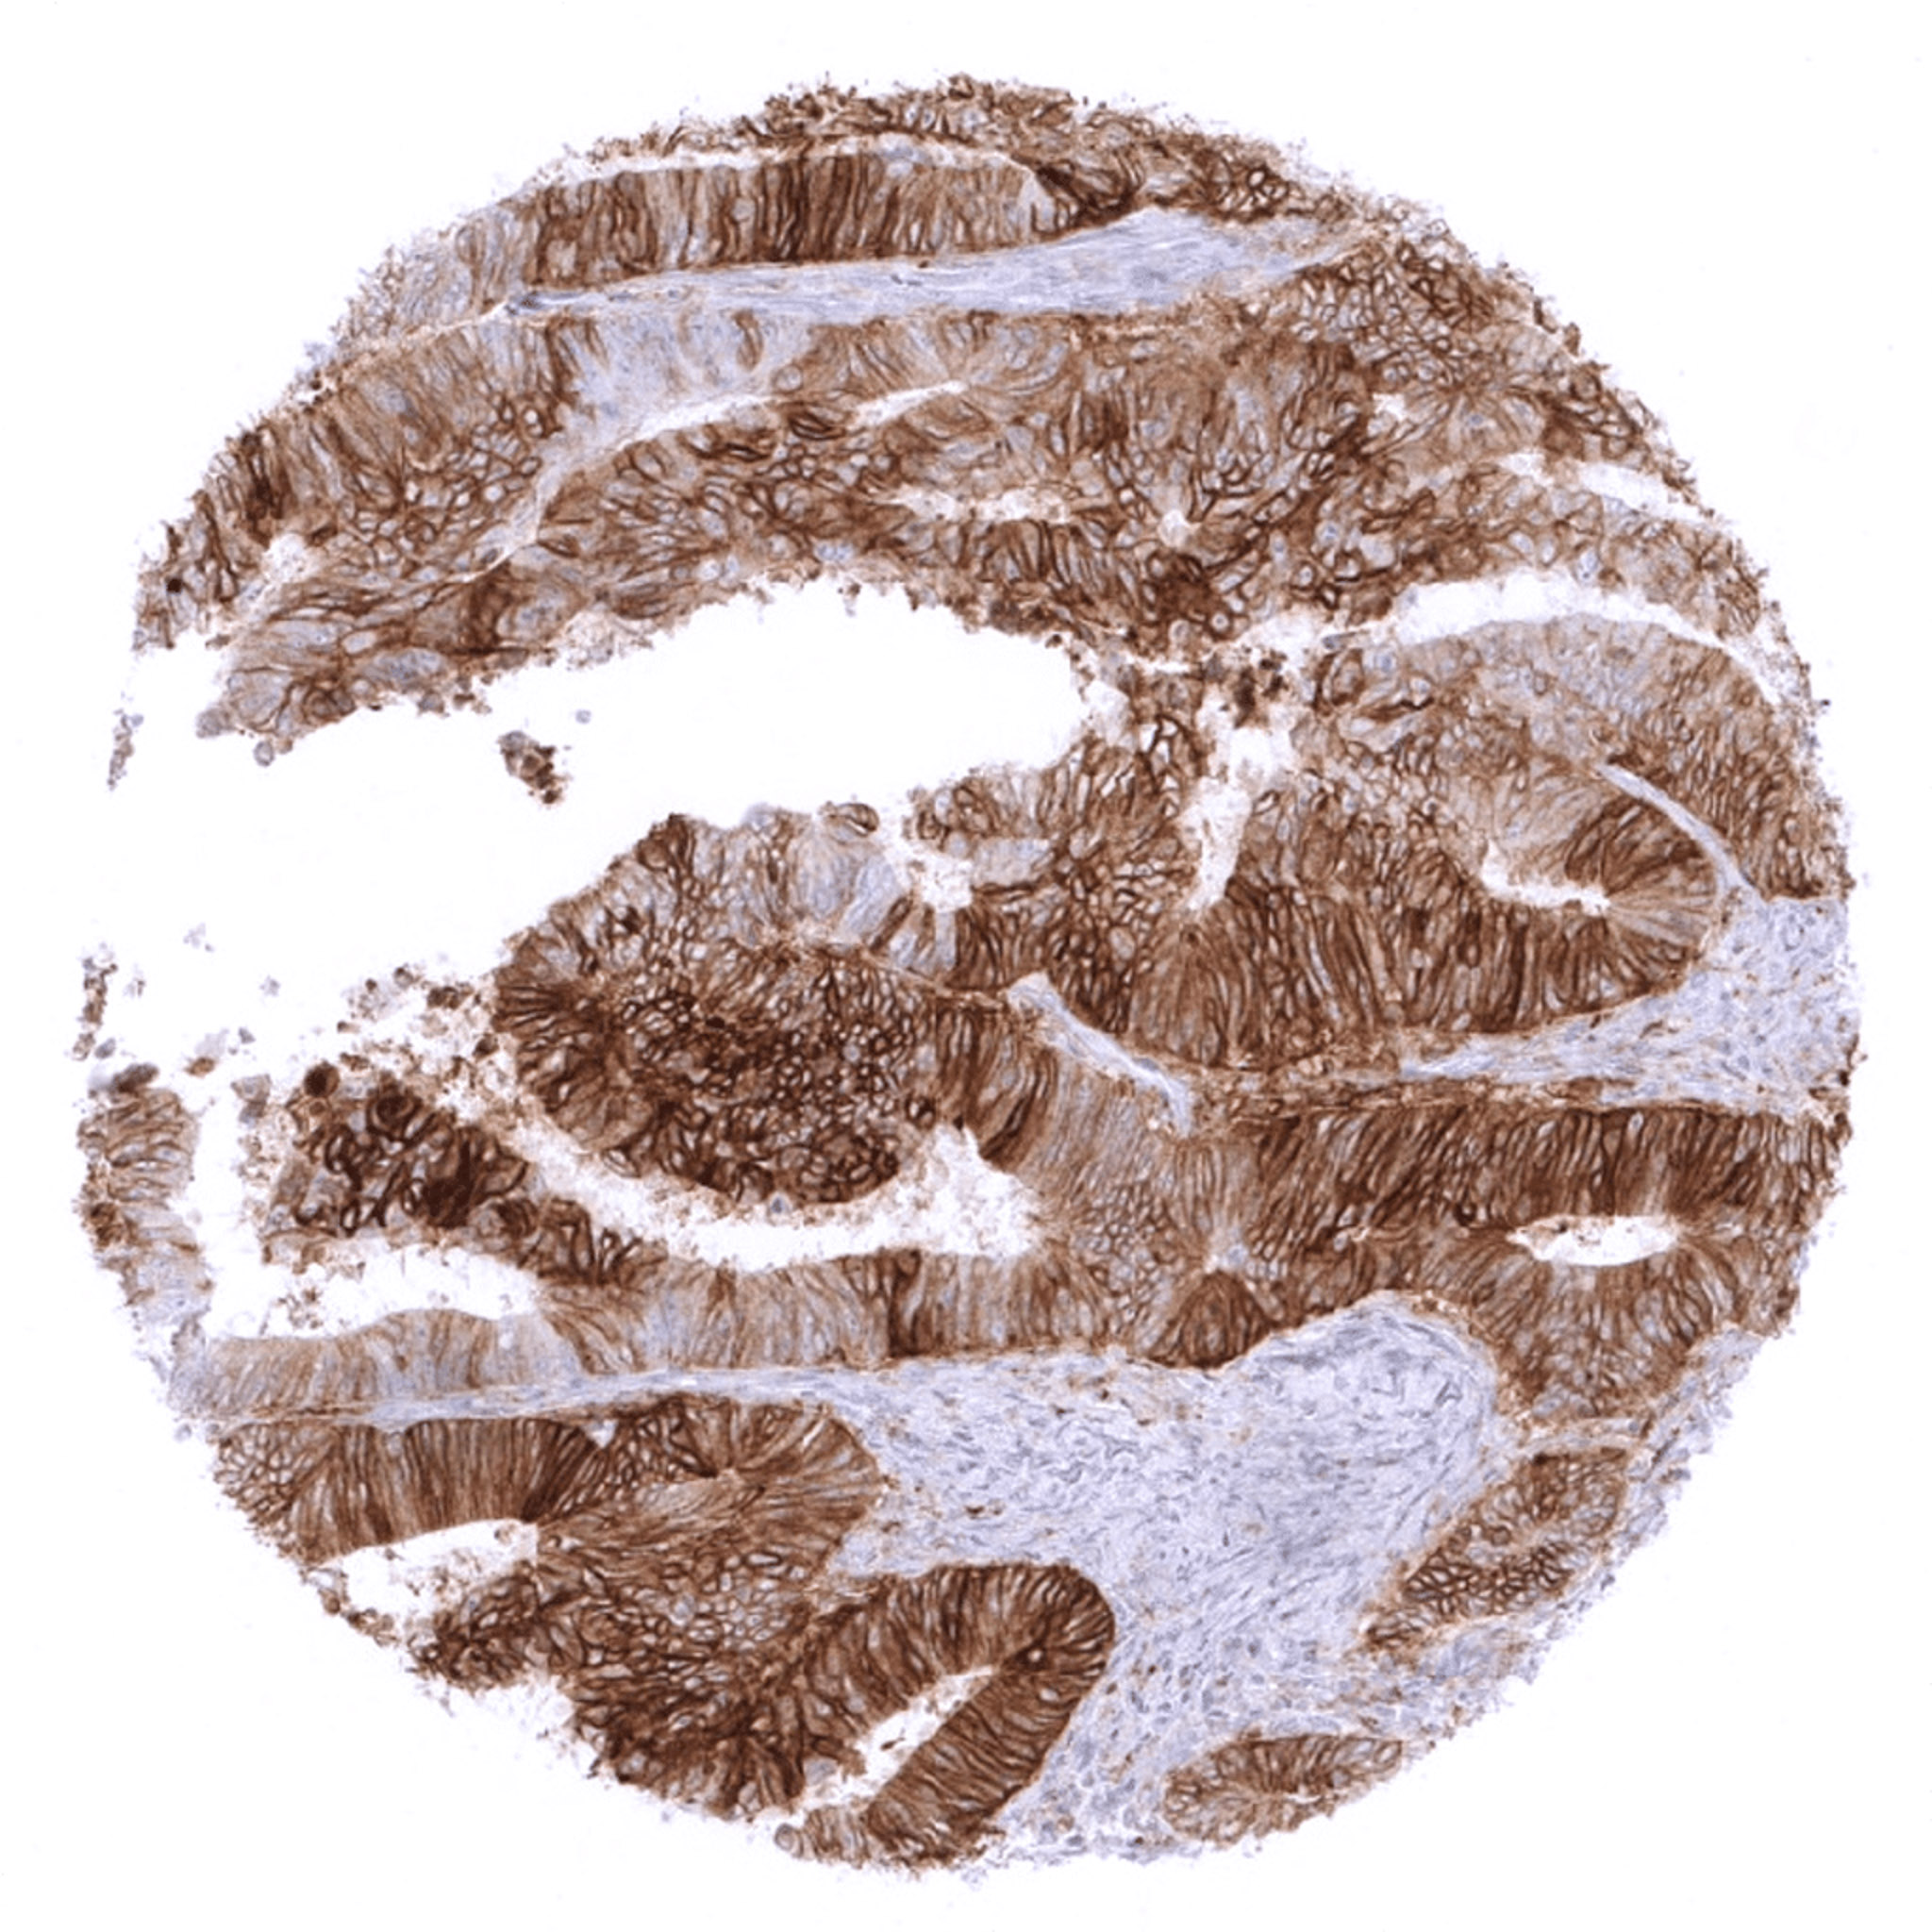

Colon – Colorectal adenocarcinoma with moderate to strong membranous PD-L1 staining in the vast majority of its tumor cells.